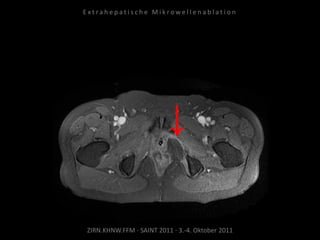

Verlaufskontrolle:

MRT 12.10.2010

Restvitalität dorsal der Harnblase.

Erneute Ablation am 04.11.2010:

2 Nadelpositionen.